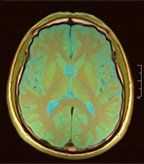

Brain MRI in a patient with lung cancer and brain metastases; Image:

© Nevit Dilmen